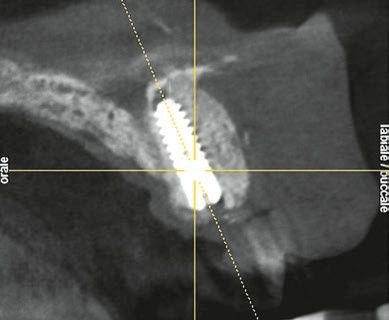

Die im Frontzahnbereich geforderte spezifische Implantatposition und die Notwendigkeit eines Schraubenzugangs auf der Palatinalfläche des Zahns machen es mitunter problematisch, innerhalb der Knochenanatomie der Prämaxilla zu platzieren. Die Folge einer solchen Position ist eine enge Lagebeziehung des Implantatapex zur vestibulären Kortikalis, verbunden mit der Gefahr einer Knochenfenestration (operativer Eingriff mit dem Ziel, ein Fenster in den Knochen zu bohren) und deren Folgen (Abb. 3).

Die Hauptachse eines zentralen Schneidezahns verläuft durch den Wurzelapex und die Schneidekante. Seine Position und Orientierung im Knochen hängen von der skelettalen Angle-Klasse des Patienten und dem parodontalen Biotyp ab. So erleichtert eine Klasse II die Implantation im Oberkiefer-Frontzahnbereich, da der Alveolarknochen stärker vertikal orientiert ist und ein Achsenverlauf durch die Palatinalfläche problemlos erreicht werden kann. Dagegen besteht bei einer Klasse III aufgrund der Neigung des Processus alveolaris nach anterior ein deutlich erhöhtes Risiko für eine apikale Perforation der vestibulären Kortikalis durch die Implantatbettbohrung1,8.